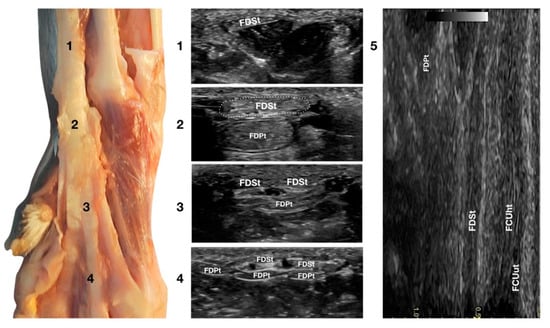

Just medial to the accessory bone, so close that in a longitudinal scan plane, a minimal medial angulation of the probe gave the impression of some degree of continuity with the FCUt; the Flexor Digitorum Superficialis tendon (FDSt) was seen parallel to the FCUt but extending distally to the accessory carpal bone (Figure 1c). On transverse images, moving the probe slightly medially to the accessory bone, the FDSt was seen as a large, echoic, elliptical structure, approximately twice as wide as thick. The Flexor Retinaculum was a thick connective layer that created a nearly uniform echoic ring surrounding the tendon and separating its deeper margin from the Flexor Digitorum Profundus tendon (FDPt) beneath (Figure 7).

Figure 7.

Palmar carpal face centred on the Flexor Digitorum Superficialis tendon. At the ulnar notch level (2), the FDSt is a broad and flattened elliptical structure surrounded by echoic ill-defined tissue (the Retinaculum). It is just superficial to the larger Flexor Digitorum Profundus tendon. Proximally, the tendon is very superficial and flat at the tenomuscular junction (1). Distally, in the proximal third of the metacarpus (3), the tendon starts to divide into four structures that diverge and follow the more profound and larger parts of the FDPt (4). On the longitudinal scan (5), obtained by putting the probe in the hollow medially to the accessory carpal bone and angling the probe slightly laterally, the fine fibrillar pattern of the FDSt is seen parallel and separated from the more lateral and superficial FCUt by fat and the Retinaculum. The deeper FDPt is barely visible since it is not perfectly parallel to the other two tendons. The FDPt starts deeper and runs obliquely to become relatively superficial at the accessory bone passage where it pairs with the FDSt until their termination.

Progressing proximally, the tendon quickly became thinner and broader, assumed a superficial position, and was separated from the FDPt by several muscle bellies. Just distal to the accessory bone, the tendon thickened and paired with the deeper FDPt. In the proximal third of the metacarpus, the FDSt flattened, becoming progressively thinner and remaining superficial to the thicker FDPt. At this level, they split into four parts that diverged from the second to the fifth metacarpophalangeal joint. At this level, the paw partially interferes with the visibility of such small structures. By elevating the foot and using the palmar aspect of the digit with a golf stick probe, it was possible to have an acoustic window distal to the paw pad. This small window often made it possible to recognise it in a transverse scan, a small elliptical structure corresponding to the fusion of the FDS and FDP tendons. A rich fibrillar tendinous pattern was noted in the longitudinal scan of the tendon. The phalangeal termination was often best visualised in the longitudinal scan plane using the palmar digital surface, and a single thin tendon, representing the combination of the FDS and the FDP tendons, was sometimes recognised and rarely followed up to the FDSt insertion at the palmar surface of the base of the middle phalanx. Flexing and extending the digits and the carpus, and stressing the carpus and the digits mediolaterally enhanced the range of motion and the degree of tendon compliance, and tested the Extensor Retinaculum function.

3.3.3. Flexor Digitorum Profundus Tendon Ultrasonographic Anatomy (FDPt)

In the hollow between the protruding portion of the accessory carpal bone and the caudal margin of the radial ulnar notch, in a transverse scan plane, the more superficial and elliptical FDSt and the deeper, larger and rounder Flexor Digitorum Profundus tendon (FDPt) were easily seen as paired structures (Figure 1d). Using an adequate amount of gel helped to align the probe with an area having an uneven surface. The thick tendon was grooved on the palmar surface of the carpus that was converted into the carpal canal by the Flexor Retinaculum surrounding the FDS and the FDP tendons (Figure 8).

Figure 8.

Palmaromedial carpal face centered on the Flexor Digitorum Profundus tendon. The FDSt were displaced to show the FDPt beneath. At the ulnar notch level (2), the FDPt is a wide, thick, oval structure, surrounded by ill-defined echoic tissue (the Retinaculum). It is just a little deeper but is in close contact with the thinner Flexor Digitorum Superficialis tendon. Proximally, at the tenomuscular junction (1), the tendon is located in a deep position. It runs obliquely distally, becoming progressively more superficial until the level of the radial notch where it pairs with the FDSt (2). At the level of the proximal third of the metacarpus, the tendon becomes thinner and wider (3) until it starts to divide into four parts that diverge and follow the superficial and thinner parts of the FDSt (4). The thin tendons of the FDS and of the FDP are outlined by the small branches of the digital veins (dv). The thick interosseous muscles (IO) separate the tendons from the third (P3), fourth (P4), and fifth (P5) metacarpal bones. On the longitudinal scan (5) obtained by putting the probe in the hollow area medial to the accessory bone and angling the probe slightly medially, the fine fibrillar pattern of the FDPt is seen, converging toward the FDSt. The more superficial FCUt and the accessory bone (AC) are barely visible.

Proximally, the FDPt ran obliquely and had a deep position, relatively closed to the caudal margin of the radius and ulna. The obliquity of the tendon with respect to the surface of the skin created the false impression of a relatively hypoechoic tendon, due to an anisotropy artefact. The tendon became parallel to the skin at the level of the accessory carpal bone and, at this level, it appeared as a large, oval, echoic structure with a rich fibrillar pattern. On the proximal portion of the metacarpus, the FDP tendon divided into four branches from digits II to V and ran distally, covered by the corresponding branches of the FDS tendon. The technique for checking the distal aspect of the tendon was the same as that previously reported for the FDSt. While the FDSt inserted into the palmar surface at the base of the middle phalanx, the FDPt inserted into the tuberosities of the distal phalanges of digits II to V. This part was only visible if accurate preparation of the palmar pad of the digits was carried out. Abundant gel was applied to an elevated pad for at least five minutes before the scanning. In some patients, the dryness and thickness of the palmar pad prevented imaging of this region. On the longitudinal scan, a dense fibrillar pattern was recognised in the proximal portion of the tendon while, in the most distal and thinner portion, the tendon appeared relatively hypoechoic and uniform, especially when the tendon thickness was less than 1 mm. The oblique path of the tendon emerging from a deep position to be parallel to the FDSt was better assessed on the longitudinal plane. The flexion and extension of the carpus and the digits, together with the mediolateral stressed poses, were used to assess adhesions, range of motion, and subluxations of the tendon.